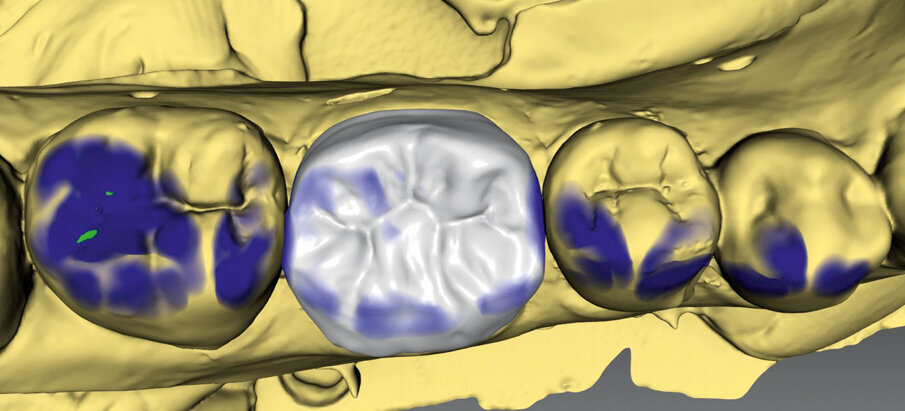

Fig. 1: Pre-op situation.

A 45-year-old male patient presented to the practice with a restoration on tooth #46. The tooth had been endodontically treated and temporised with a filling (Fig. 1). The temporary was removed, the tooth built up with Tetric N-Ceram Bulk Fill (Ivoclar Vivadent) and then prepared for the crown restoration (Fig. 2). An impression was taken with a one- step, two-phase impression technique using a putty and light-body silicone. After scanning the model, the crown was designed in the software suite (inLab, Dentsply Sirona) and milled from an IPS e.max CAD lithium disilicate block (Ivoclar Vivadent; Figs.3a & b). After the crystallisation fir- ing, the crown was stained and glazed (Fig. 4). The next step was to etch and silanate the ceramic crown with the new glass-ceramic primer Monobond Etch & Prime (Ivoclar Vivadent). This primer combines a ceramic etching and silanating component in a single material and therefore eliminates the need for the ceramic to undergo hydrofluoric acid etching (Fig. 5). After the etching and silanating step, the crown was rinsed with water and dried. The isolated enamel was then etched (Fig. 6). The adhesive (Tetric N-Bond Universal) was applied and dispersed with a strong stream of air. The dual-curing version of the Variolink Esthetic luting composite was used for seating owing to the thickness of the crown and the low translucency of the ceramic material (Fig. 7). The luting composite was applied into the crown. The restoration was then seated (Fig. 8) and light-cured from each side for two seconds. Excess composite was easy to remove owing to the Ivocerin photoinitiator (Ivoclar Vivadent), which provides a fast and thorough cure with a minimum amount of energy (Fig. 9). For final polymerisation, the restoration was light-cured from each quarter for 20 seconds (Fig. 10). Figures 11 and 12a & b show the oral situation after placement of the crown. Although the cement line was located above the gingival margin, it was not visible owing to the favourable tone and opacity of the luting composite. Figures 13a & b show radiographic control images of the restoration: the radiopaque build-up material and cement can easily be distinguished from the tooth structure. This aspect is particularly important in situations where excess cement cannot be seen with the naked eye.